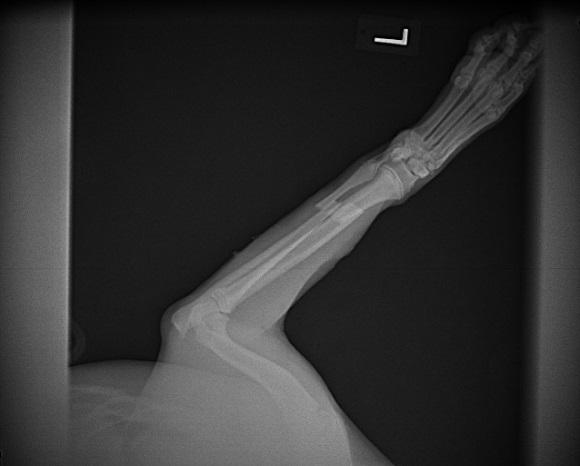

Loki’s fracture before and after surgery… This is a picture of the fracture. This is a Transverse (straight) fracture of his radius and ulna. These images are post surgery checking for appropriate pin placement and alignment of the fracture.

This is a picture of the fracture.

This is a Transverse (straight) fracture of his radius and ulna